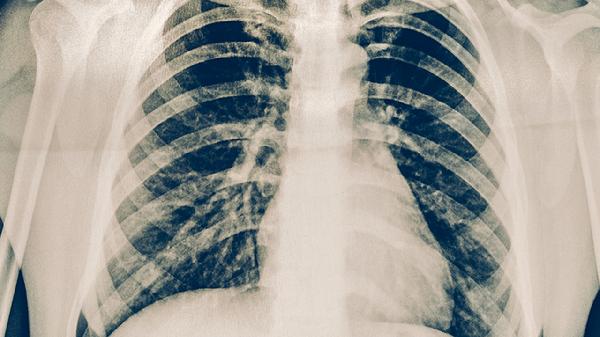

血行播散型肺结核通常由结核分枝杆菌通过血液播散至全身引起,常见于免疫力严重低下者。该类型起病急骤,可能出现高热、寒战、呼吸困难等症状。胸部影像学检查可见双肺弥漫性粟粒样结节。治疗需联合使用乙胺丁醇片、链霉素注射液等药物,重症患者需住院治疗。